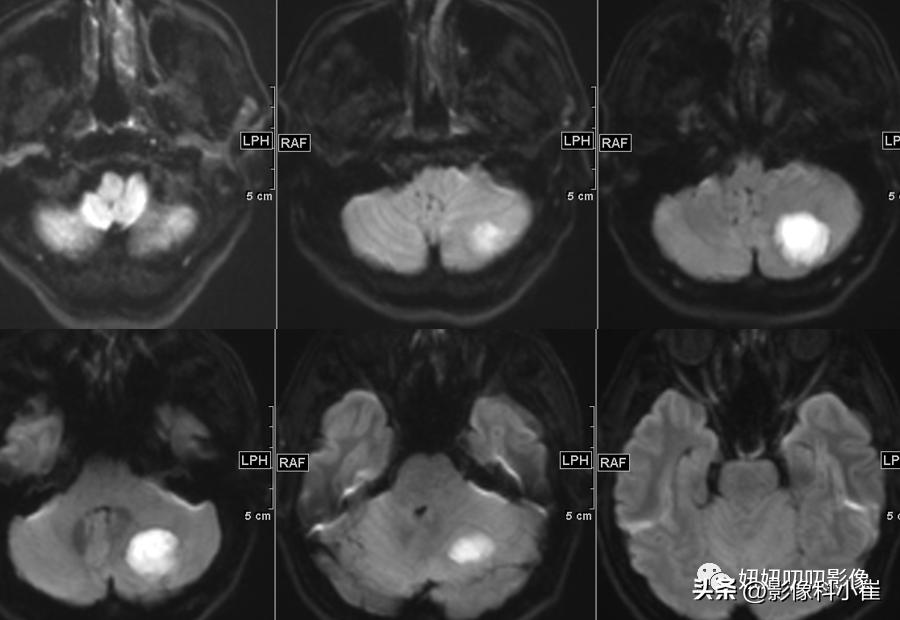

左侧小脑半球片状长短T1等长T2 异常信号,边界不清,大小约3.2X2.9X2.4cm,T2-Flair呈等高信号,周围见斑片状水肿带,DWI 示病变明显弥散受限,增强扫描可见不均匀环状强化。双侧放射冠、皮层下另见少许斑点状等长 T1、长T2 异常信号灶,T2 Flair 呈高信号,DWI未见明显弥散受限,增强扫描未见明显异常强化。第四脑室受压变窄,幕上脑室系统未见明显扩张。脑沟、脑裂略增宽。中线结构无移位。双侧筛窦、上领窦粘膜增厚。

这个病有意思,周边T2黑黑的,弥散受限这么明显,强化还是环形强化,从环形强化入手?转移,胶质母,脓肿。从弥散收入,淋巴瘤,脓肿,胶质母,T1还有出血,信号不均匀,边界清楚。其实看到出血觉得是胶质母,其实看看弥散的均匀度,和环状强化的边,并不是那么花环样子,加上白细胞高,可能还是脓肿。